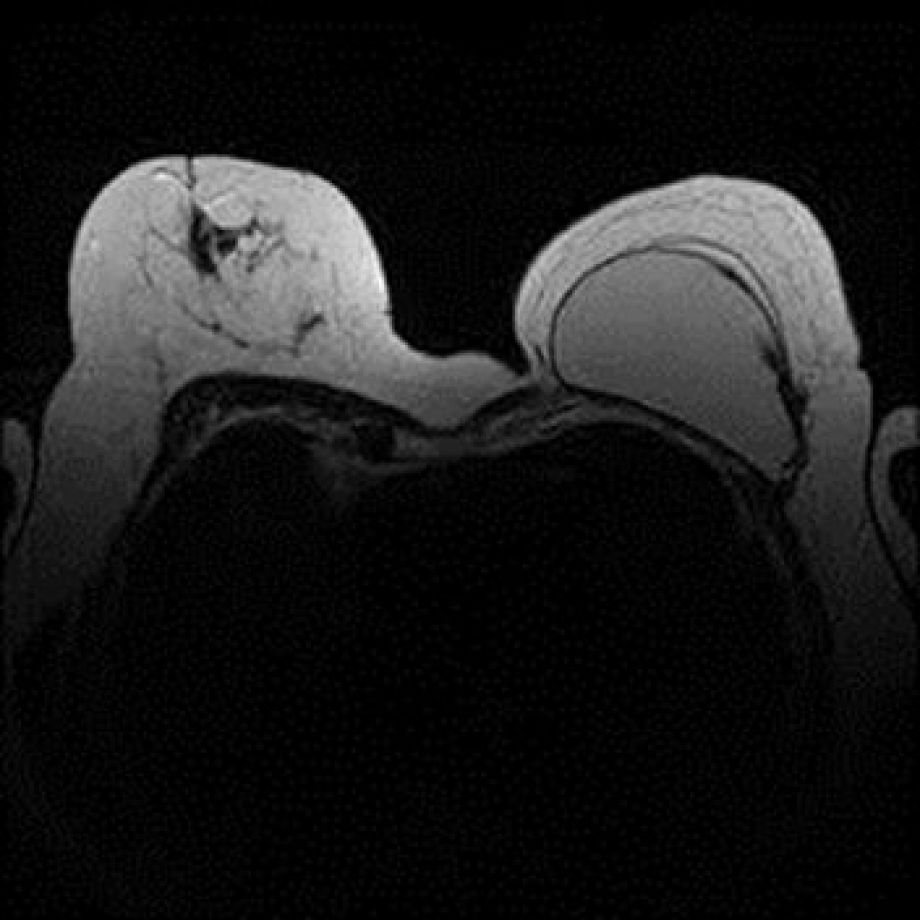

IRM, Scanner, radiographie, échographie, Doppler, Mammographie,Infiltration, Ponction et imagerie interventionnelle, Conebeam